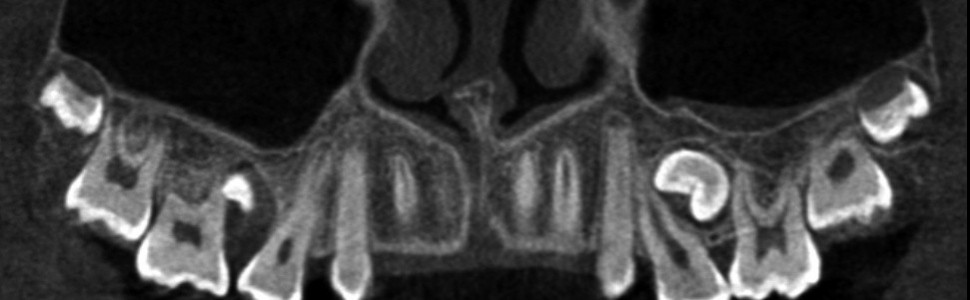

Resorpcja zęba to proces powstania ubytku twardych struktur zęba wywołanego przez osteoklasty bez kontaktu ze środowiskiem jamy ustnej, między innymi na skutek ucisku wywieranego przez ząb zatrzymany. Dla lekarza ortodonty jest istotne ustalenie, czy zęby zatrzymane lub twory nadliczbowe powodują resorpcję zębów stojących w łuku w celu wczesnej eliminacji przyczyny resorpcji. Celem pracy jest przedstawienie opisu przypadku zastosowania tomografii stożkowej w diagnostyce nieprawidłowo położonych zawiązków zębów przedtrzonowych drugich górnych. Stwierdzono, że tomografia stożkowa jest skuteczną metodą oceny wczesnej resorpcji zewnętrznej korzeni zębów.

Tooth resorption is the process of appearing of a defect of hard tissues of teeth caused by osteoclasts not having contact with oral cavity environment, eg. due to mechanical pressure exerted by an impacted tooth. It is essential for an orthodontist whether impacted teeth or supplementary teeth cause resorption of erupted teeth in order to early eliminate the causative factor of the resorption. The aim of the paper is to describe a case report of cone-beam computed tomography (CBCT) in diagnostics of incorrectly located germs of upper second premolars. It was found that CBCT was an efficient method of imaging of early external root resorption.